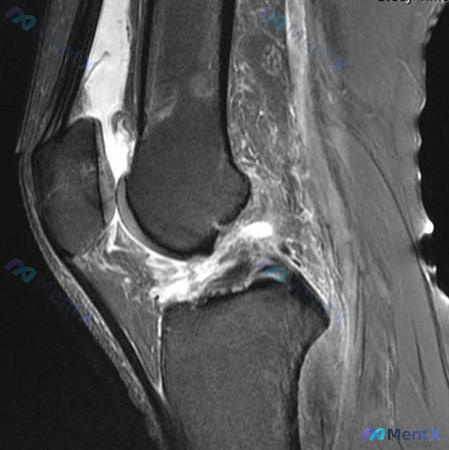

看到一个挺有警示意义的病例,整理了一下思路和大家分享。 病例基本情况 患者是一名 30岁的网球运动员,因膝关节损伤就诊,目前正在评估受影响结构的非手术治疗方案。核心问题是:哪一项临床发现与非手术治疗后关节炎变化的未来发展相关性最强? 影像与关键发现(基于提供的MRI) 这是一个矢状位的序列,从信号特...